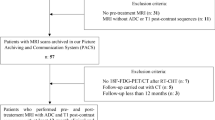

Institutional research ethics board approval was obtained, and written informed consent was waived for this retrospective study. Consecutive patients with NPC, who underwent MRI between October 2012 to August 2014, were identified from the Picture Archiving and Communication System of our institution. The inclusion criteria were (a) patients with primary NPC that was confirmed by histological biopsy, (b) patients who underwent nasopharyngeal-neck MRI within 2 weeks before treatment and (c) patients who achieved a complete response after treatment. A total of 116 patients met the inclusion criteria. Patients were excluded if they (a) had other malignancies (n = 3) or distant metastases at diagnosis (n = 1), (b) had a primary tumour merely confined to nasopharyngeal mucous but without mass formation (n = 17) or (c) had incomplete follow-up data (n = 16). Finally, 79 NPC patients (52 men and 27 women; mean age, 46.6; age range, 15–73 years) were included in this study.

Two radiologists with 6 years (J.F.) and 10 years (X.D.) of experience in diagnostic MRI assessed all images for each patient and staged the tumour according to the established staging system by consensus [19]. For the texture analysis, all axial T2WIs and CE-T1WIs were individually transferred to the in-house texture analysis software package (Omni-Kinetics Version 2.1, GE Healthcare) [20]. A free-hand region of interest (ROI) was manually drawn to delineate the whole tumour on each slice by a radiologist with 6 years of experience (J.M.). Three-dimensional segmentation of the tumours was then completed automatically by the Omni-Kinetics software package. Each segmentation was checked and validated by a senior radiologist with 23 years of experience (J.S.). The obtained volume of interest for each lesion was executed, and values of texture features were calculated. The first-order and second-order texture features were then obtained by using histogram analysis and grey-level co-occurrence matrix (GLCM), respectively. Five first-order texture parameters (histogram features) including entropy, uniformity, variance, skewness and kurtosis, together with four second-order texture parameters (GLCM features) including GLCM entropy, angular second moment (ASM), cluster prominence and cluster shade were chosen to measure NPC heterogeneity in our study. The texture features included are described in detail in Supplementary Table 2. The schematic diagram for data processing is shown in Fig. 1.